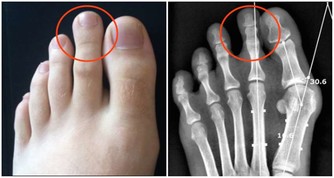

人體十二經脈的起點或終點都在身體末梢,其中六條走到雙手,停在十根指頭,打開手心有三條陰經走到大拇指、中指、小姆指翻到手背則有三條陽經走到食指、無名指、小姆指,而另外六條通達腳趾的經脈也可以透過相似的經氣,在手上得到表裡的對應。

雙手匯通全身經脈,

既然雙手與五臟六腑密切連結,我們其實可以不用等到頭痛、胃痛、肚子痛……等身體不舒服的時候再頭昏眼花的比對著穴位圖,而是從平常就開始捏捏手保健康。